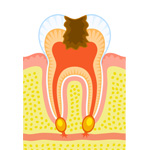

根管治療

歯の中心部に細菌が入り込むと、根管治療を行わなくてはなりません。根管治療には丁寧な施術が不可欠です。当院では、1回の治療に1時間以上かけて確実に行っています。

虫歯が進行して歯の中心にある歯髄部分にまで達してしまうと、根管治療が必要となります。しかし、この歯髄部分は非常に細く、曲がっています。その曲がり方も人によって違うので、きちんと治療するのは大変難しいのです。

歯髄に細菌が入り込んでしまうと、細菌によって腐ってしまった部分を取り除くだけでは終わりません。周囲の歯髄にも細菌が入り込んでいる可能性があるので、リーマーやファイルといった細い器具で、歯髄部分を全部掻き出す必要があります。

時間をかけて確実に治療

根管治療を行ったにも関わらず、しばらくするとまた歯が痛み出すことがあります。原因は、根管部分に細菌が残ってしまい、中で再び繁殖してしまったこと。その場合、歯に被せた冠を取って、根管治療をやり直します。

そういった事態を避けるためには、根管治療をしっかりと丁寧に行うしか方法はありません。当院では確実に歯髄を取り、徹底的に除菌するため、1回の根管治療に1時間以上かけてしっかりと行っています。症例によっては2時間近くかかることもありますが、確実な治療のためとご理解いただければ幸いです。

技術と経験で、患者さまの負担を軽減

根管治療は非常に難しく時間がかかる施術なので、通常は数回に分けて行われます。しかし、患者さまはそのために何度も通院しなければなりません。さらに、根管治療を行っている間は、その歯に被せ物をするわけにもいかないので、食事などにも不便です。

根管治療は非常に難しく時間がかかる施術なので、通常は数回に分けて行われます。しかし、患者さまはそのために何度も通院しなければなりません。さらに、根管治療を行っている間は、その歯に被せ物をするわけにもいかないので、食事などにも不便です。

当院では、そういった患者さまのさまざまな負担を考え、少ない治療回数で根管治療を終わらせています。当院のドクターは、今までに多数の症例を手がけてきた根管治療の専門家です。豊富な経験から培った確かなテクニックで、少ない治療回数で細菌に感染した部分を確実に取り去り、除菌します。

時間をかけた施術が必要な根管治療は、患者さまにとっても負担です。当院では経験から培われた確かな技術で、できるだけ少ない治療回数で根管治療を終わらせます。

みなさまは「根管治療」という言葉を聞いたことがありますか?歯の中心にある歯髄は管状になっていて、中には神経や毛細血管がとおっています。この管状の部分を根管と言います。虫歯が進行して歯の中心部である歯髄にまで達してしまったとき、あるいは歯の根の病気にかかったときに、根管治療が必要となります。

しかしこの根管治療は難しく、時間もかかります。なぜ根管治療はそれほど難しいのでしょうか。

時間のかかる根管治療

根管の中はとても細いので、直接目で見ることができません。しかも根管の形はまっすぐではなく、人によってそれぞれ曲がり方が違います。そのため内部に細菌が入ってしまうと、きれいに取り除くことが難しくなってしまうのです。

たとえ根管治療を行っても、中に細菌が残ったまま詰め物や被せ物をすると、歯の内部で細菌が増殖して新たなトラブルを引き起こしてしまいます。そのため、細菌を取り除くためには時間をかけて丁寧に治療するしかありません。場合によっては、患者さまは何度も歯科医院に通うことになってしまうのです。

少ない回数で治療を終わらせる技術と経験

当院では、さまざまな面から患者さまの負担を考え、できるだけ少ない治療回数で根管治療を終わらせています。症状によっては、1回で終わらせることも可能です。ただし、1回の診療にかかる時間は1時間以上と、ちょっと長めです。

当院では、さまざまな面から患者さまの負担を考え、できるだけ少ない治療回数で根管治療を終わらせています。症状によっては、1回で終わらせることも可能です。ただし、1回の診療にかかる時間は1時間以上と、ちょっと長めです。

当院のドクターは、根管治療の症例をいくつも手がけてきた専門家です。確かな技術と豊富な経験から、少ない治療回数で、細菌に感染した部分を再発しないようにきちんと取り去り、除菌します。何回にも分けて根管治療を行うと、治療の間に残った細菌が繁殖してしまうことがあります。そのため、少ない回数で治療を終わらせることがベストなのです。